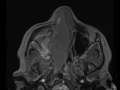

Nasal Squamous Cell Carcinoma

There is a large T1 isointense, T2 hypointense, mildly enhancing mass in the right nasal passage extending posteriorly to fill the nasopharynx and bowing the nasal septum leftward. There is mass effect and displacement of the right maxillary sinus medial wall into the sinus cavity with small areas of dehiscence in the posterior aspect secondary to the mass. The inferior aspect of the right ethmoid sinuses are involved and are expanded and right medial and inferior turbinates can not be visualized separate from this mass compatible with osseous and soft tissue destruction. The mass obstructs the right maxillary sinus, visualized right ethmoid sinuses, right sphenoid and right frontal sinuses. This pattern is consistent with a sinonasal malignancy which on biopsy turned out to be a squamous cell carcinoma (SCCa), the most common sinonasal malignancy. As seen here, SCCa does not enhance to the degree of adenocarcinoma, melanoma, or esthesioneuroblastoma and is relatively T2 hypointense.